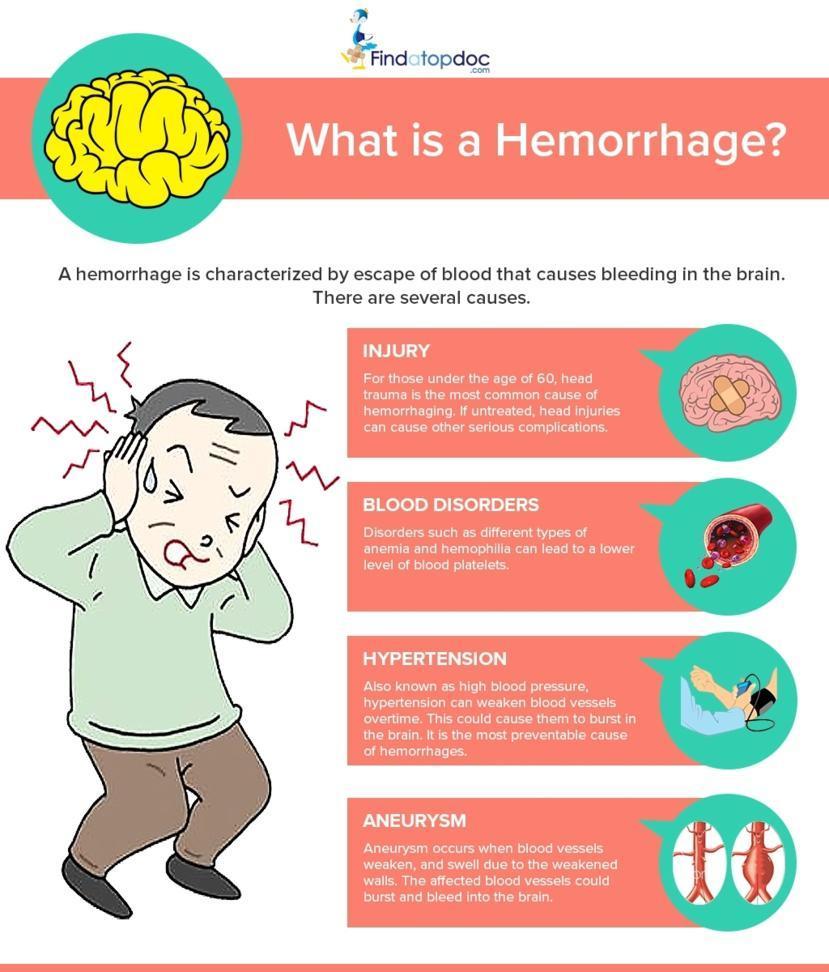

Hemorrhagic Stroke Treatment Symptoms Prognosis Recovery Learn what causes a hemorrhagic stroke and how it differs from an ischemic stroke in its symptoms, treatment, life expectancy, and prevention. Hemorrhage 1 of 2 noun hem· or· rhage ˈhem (ə )rij : a great loss of blood from the blood vessels especially when caused by injury hemorrhagic ˌhem ə ˈraj ik adjective hemorrhage 2 of 2 verb. Hemorrhage is a medical term that describes any type of bleeding from a damaged blood vessel. it can be minor or severe and external or internal. Hemorrhage is the medical term for bleeding. it most often refers to excessive bleeding. hemorrhagic diseases are caused by bleeding, or they result in bleeding (hemorrhaging).

Spontaneous Intracerebral Hemorrhage Pathogenesis Clinical Features Hemorrhage is a medical term that describes any type of bleeding from a damaged blood vessel. it can be minor or severe and external or internal. Hemorrhage is the medical term for bleeding. it most often refers to excessive bleeding. hemorrhagic diseases are caused by bleeding, or they result in bleeding (hemorrhaging). What is a haemorrhagic stroke? haemorrhagic stroke is when you have bleeding in or around the brain. this can damage brain cells. damage to brain cells can affect how the body works. it can also change how you think, communicate and feel. The most serious level of hemorrhage is hemorrhagic shock, a medical emergency that can quickly turn fatal. 2 hemorrhagic shock is when the body loses so much blood that the heart cannot keep up, and vital systems begin failing. Most adults can lose up to 14% of their blood volume without physical symptoms or deviations in vital signs. however, blood pressure drops significantly if a person loses more than 30% of their blood volume. severe hemorrhaging means that a person’s tissue will not supply sufficient oxygen. this can lead to hemorrhagic shock and possibly death. A hemorrhagic stroke occurs when a weakened blood vessel ruptures. it makes up about 13% of all stroke cases. learn the warning signs here.

Hemorrhagic Stroke Intracerebral Hemorrhage Subarachnoid Hemorrhage What is a haemorrhagic stroke? haemorrhagic stroke is when you have bleeding in or around the brain. this can damage brain cells. damage to brain cells can affect how the body works. it can also change how you think, communicate and feel. The most serious level of hemorrhage is hemorrhagic shock, a medical emergency that can quickly turn fatal. 2 hemorrhagic shock is when the body loses so much blood that the heart cannot keep up, and vital systems begin failing. Most adults can lose up to 14% of their blood volume without physical symptoms or deviations in vital signs. however, blood pressure drops significantly if a person loses more than 30% of their blood volume. severe hemorrhaging means that a person’s tissue will not supply sufficient oxygen. this can lead to hemorrhagic shock and possibly death. A hemorrhagic stroke occurs when a weakened blood vessel ruptures. it makes up about 13% of all stroke cases. learn the warning signs here.